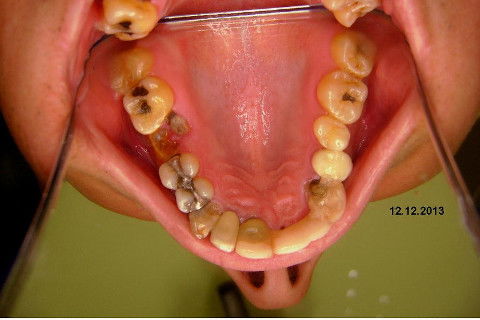

Paciente apareceu em meu consultório em dezembro/2013 para resolver problema de insatisfação com ponte fixa provisória anterior, realizada há 9 anos atrás (2004)...pretendia realizar somente a reabilitação em maxila/anterior, não contava com outros problemas com maior gravidade na sua boca, o máximo que citou foi a indicação para a exodontia do 16...

O meu planejamento já está decidido junto com o paciente somente trabalhos provisórios sobre implantes mesmo na região anterior, até que ele resolva pela reabilitação total. "Carro com pneu careca é para trocar os 4, não adianta colocar só 2..."